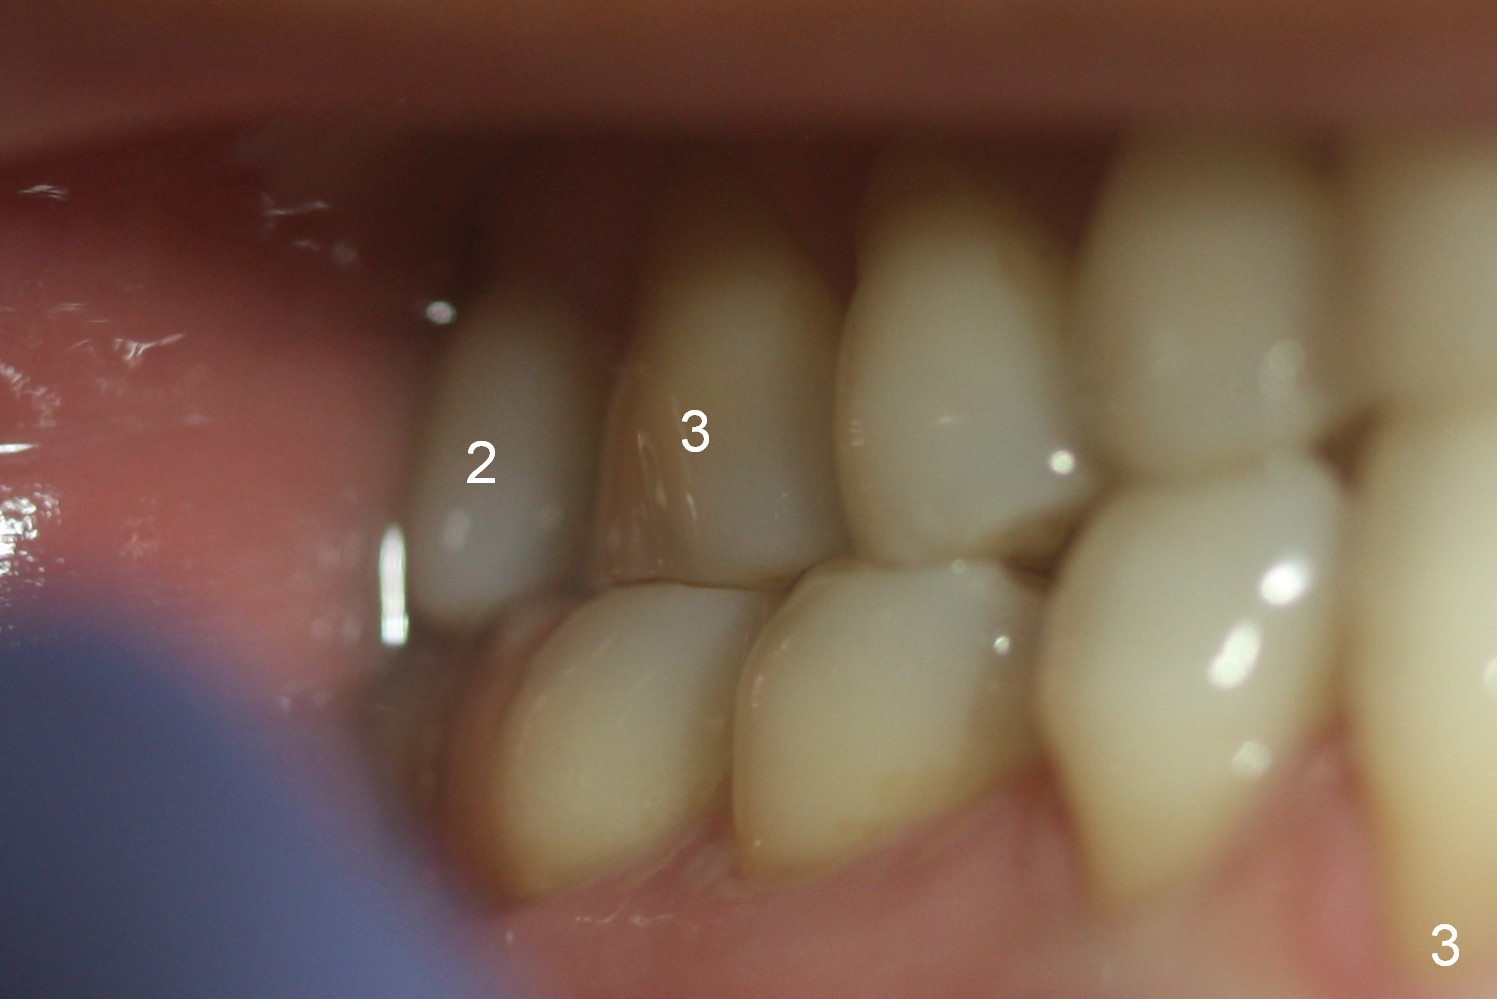

A 54-year-old woman had #14 extracted in China 1 year ago (Fig.1,5). The tooth #15 has undergone mesial shift and tilt (Fig.2,4, as compared to Fig.3). The edentulous space is too narrow for implant placement (Fig.6). It appears that traditional orthodontic appliance should be placed from UR6 to UL7 in addition to a mini-implant distal to UL7. Take Alginate impression before treatment. Since the implant at UR7 is placed apparently too deep, a band will be placed when it is initially osteointegrated (6-8 weeks postop). Fabricate a well-fit provisional with permanent cementation before banding. In fact, brackets and bands are placed between UR3 and UL7. In 6 months, the meisodistal space at #14 is enough to place an implant (Fig.7).